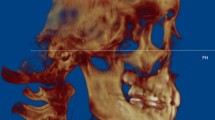

The superior limit of the condyle was determined where the first radiopaque point appeared in the joint space (Fig. 1A, B); The inferior limit of condyle was determined when the sigmoid notch which is between the mandibular condyle and the coronoid process disappeared (Fig. 1C, D). After determination of the conture of interest (VOI), an appropriate greyscale cut-off value was manually selected by scrolling the coronal slices of the condyle so that the condyle contour was visualized. Using this greyscale cut-off value, the contour of VOI was enhanced automatically (Fig. 2A). Then, made a fine adjustments manually by shading or erasing the under-contoured and over-contoured voxels using the function of EditMask. (Fig. 2B) [18]. After the isolation, three-dimensional reconstructions were performed for each condyle using a Mimics tool of calculating 3D from a mask (Fig. 3A, B). The height, superficial area, and volume were measured on the 3-D models, as has been described in previous studies [14, 19].

Condylar head height(H1) increased significantly post-treatment (P < 0.05, Table 1). BMD showed a significant decrease in the maximum axil section, the maximum sagittal section, 3D condyle and condylar head (P < 0.01, Table 2). Evaluation of volumetric measurements revealed that 3D condyle volume (P < 0.01, Table 3) and condylar head volume decreased significantly post-treatment (P < 0.05, Table 3). No significant difference was found in other measurements (P > 0.05, Tables 1, 4). Superimposed pre-treatment and post-treatment images showed both bone formation and resorption on the surface of condyle (Fig. 4).

For a comprehensive assessment of condylar surface changes, the utilization of 3D reconstructed images and a superimposition method is indispensable. 3D surface images provide a more precise representation of condylar remodeling compared to conventional 2D images. In the current study, the superimposition of pre-treatment and post-treatment 3D reconstructed images revealed that both bone formation and bone resorption had transpired on the condyle’s surface. This suggests an ongoing adaptation process to the altered TMJ environment.